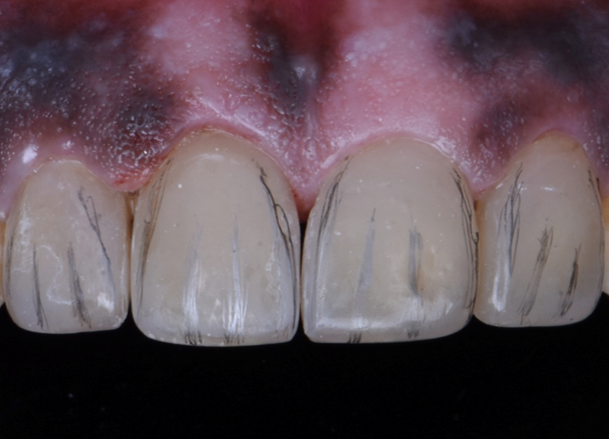

Step 6 – Contouring Restorations were marked with graphite to highlight transitional lines, mesial - distal inclination and developmental grooves. Gross three dimensional contouring was done using diamond burs. Interdental finishing strips were used to remove excess and shape emergence profile of the teeth.